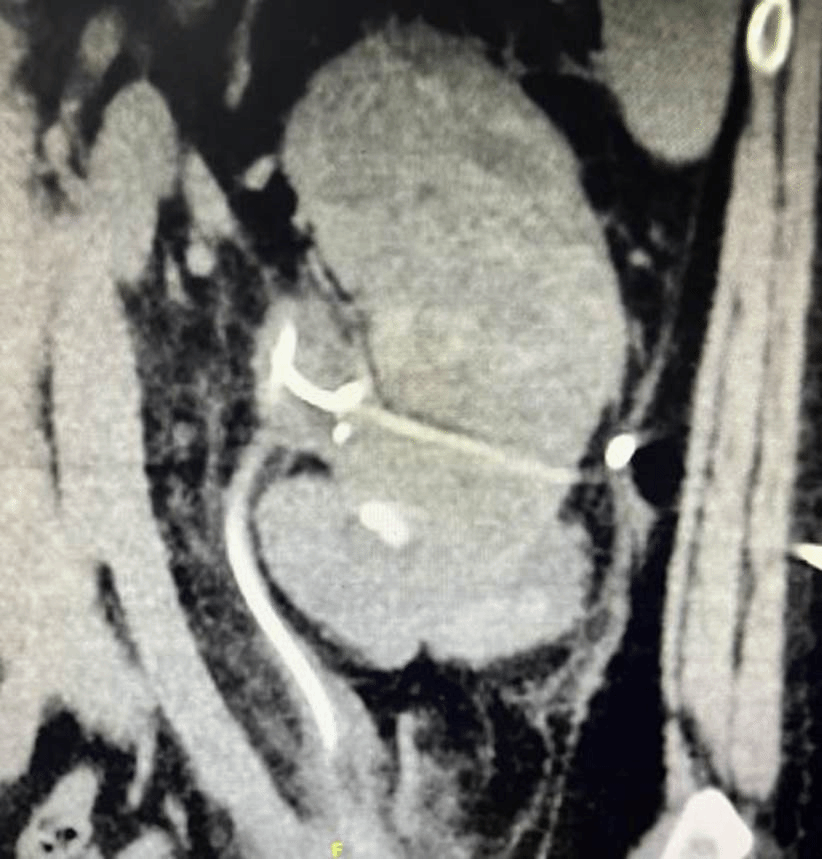

患者肿大的脓肾

12月11日,在秦某全面好转即将出院之时,患者体温再次升至39℃,经超声检查提示左肾血流明显减少,体积显著增大,脓肿形成可能性大。考虑到患者反复感染,经典抗生素治疗和保守引流无法奏效,王春阳教授团队决定拟行后腹腔镜左肾切除术。